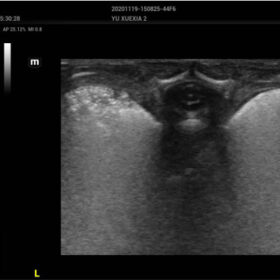

Comprehensive Imaging Solutions Powered by ZST+

The ZST+ platform is a remarkable advancement, marking a significant evolution in ultrasound technology. It revolutionizes the processing of ultrasound metrics, moving away from the traditional beam-forming approach to channel data-based processing. This breakthrough eliminates the longstanding trade-off challenges between spatial resolution, temporal resolution, and tissue uniformity. The result is outstanding image quality, providing limitless imaging solutions with continuous enhancements.

- Smart HRI– Automatic regognition of liver and renal cortex and brightness ratio calculation

- iTouch+ – real time dynamic image optimization

- Smart Calc – Automatic Trace, measurement and calculation tool

- NTE – ROI stiffness display with “Shell” quantitive assesment

- HD-Scope – improving diagnostic confidence of minor lessions

- Dehaze-improving image contrast resolution with deep presentation

- HR-Flow Improving the hemodynamic presentation